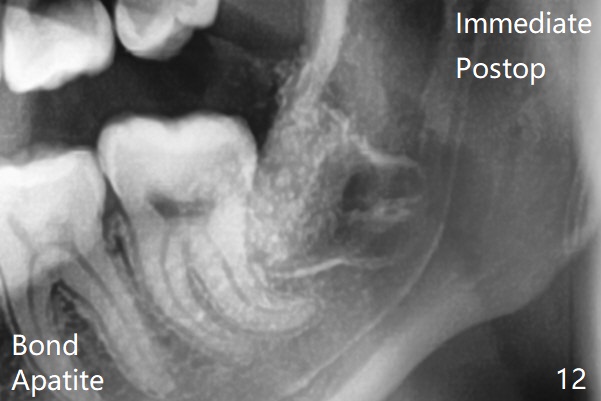

18岁女要求上大学前拔除智齿(图二),十三岁上四已经为了矫正而拔除(图一),所以现在只需要拔除下八,后者接近水平阻生,冠部可能位于下七远中颊侧(图三,四 *),所以附加切口应在七近中(红线)。智齿拔除后根部有两个牙槽窝(图五,六 *)。在右侧,塞入两个胶原塞(图七:1,2,collagen plug),其中一个末端剪开塞入根部牙槽窝。而左侧,使用一个胶原塞,但事先剪成两半(图八:1,3),第一部分也剪成燕尾,插入根部牙槽窝(1),然后在七远中放置骨水泥(1 cc Bond Apatite,2 红色),在后者上面放入胶原塞另外一半(3)。最后两侧都使用4-0 PGA 缝线。

使用胶原塞目的是预防干槽症,以前病例显示它促进骨化中心形成。骨水泥是一种医用性石膏(Biphasic Calcium Sulphate 硫酸钙 ),容易被身体吸收,3个月转换成自体骨。她哥哥(19岁)病例显示骨水泥与Osteogen Plug同样五个月会形成骨质。以后年轻人(25岁以下)智齿拔除不必植骨或者放置骨水泥。左下,右下智齿的确位于第二磨牙颊侧,事先附加切口近中,缝合后伤口不易裂开,骨粉丢失。拔除后即刻拍摄根尖片(图九,十),目的建立原有解剖,与愈合后比较,意外发现断裂牙片(F),后来取出。